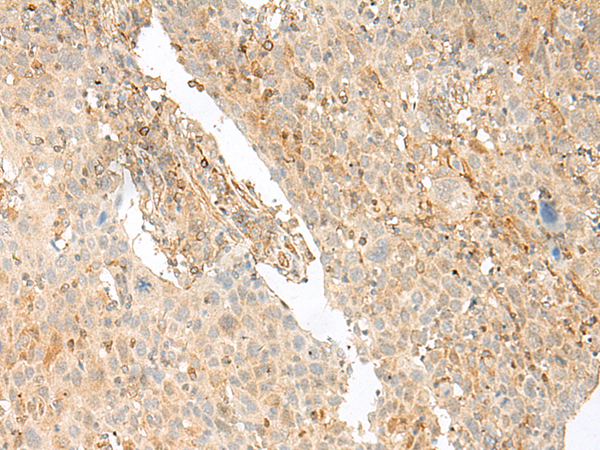

分类: 科研抗体货号: P13457别名: TAMALIN应用: IHC反应种属: Human, Mouse, Rat